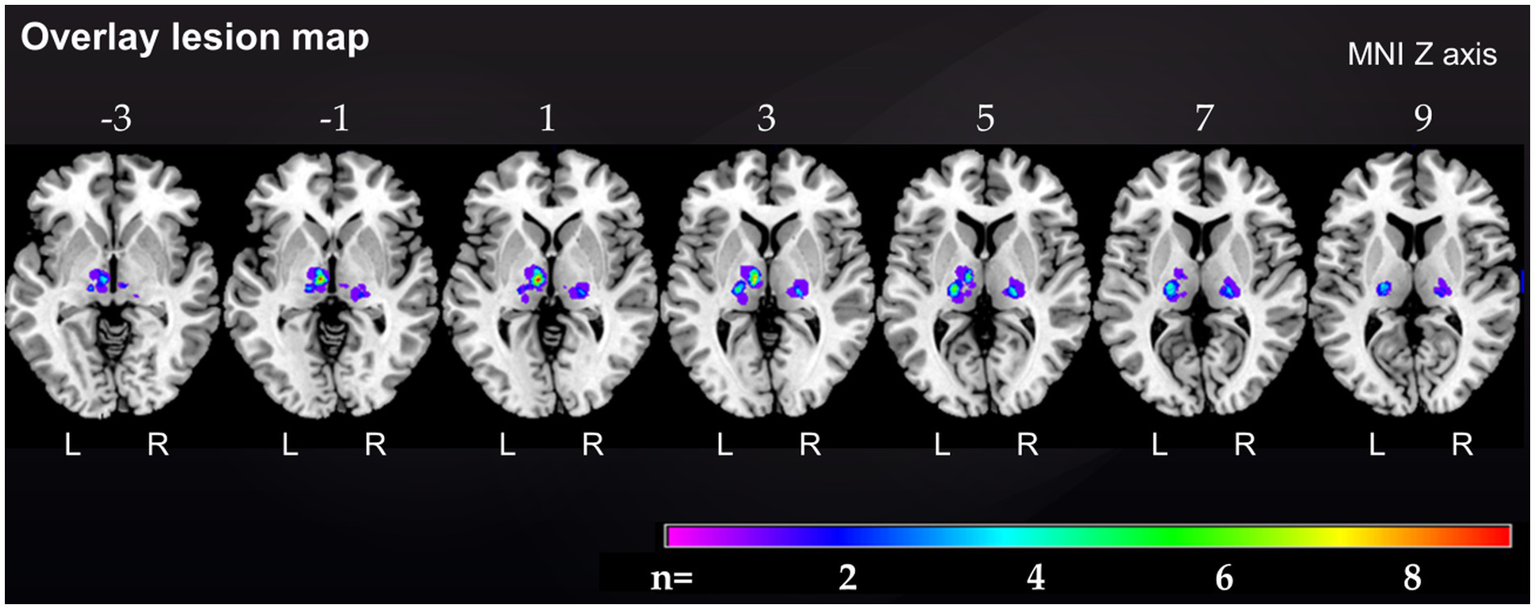

Demographic and clinical characteristics of stroke patients and their corresponding matched controls are provided in Table 1. The median age of the 37 thalamic stroke patients was 57.0 (50.0, 69.5) years [median (Q1; Q3)], 21 thalamic stroke patients were males, 27 (71.7%) patients had left, 9 (24.3%) had right and 1 (2.6%) had bilateral thalamic stroke. The lesion overlap map of all 37 thalamic strokes (Figure 1) showed that the thalamic regions most often affected were in the left central thalamus (X = −8, Y = −14, Z = 1) with 9 patients showing overlapping lesions. In the left (X = −19, Y = −19, Z = 7) and right (X = 20, Y = −21, Z = 3) inferolateral thalamus, 5 patients each showed overlapping lesions. Inferolateral thalamic stroke patients had significantly more often hyperlipoproteinemia (65.0%) than their matched controls (25.0%, p = 0.011). Lesion volume, history of depression, EBI and mRS did not differ between vascular territories affected (Table 1 and Supplementary Table S1). Neurological and cognitive characteristics of the study cohort have been described previously (Scharf et al., 2022).

Figure 1

Overlap lesion map of all 37 thalamic stroke patients. The color bar indicates the frequency of lesion overlap in thalamic stroke patients. Numbers above each brain section indicate MNI Z axis. MNI, Montreal Neurological Institute, R, right; L, left.